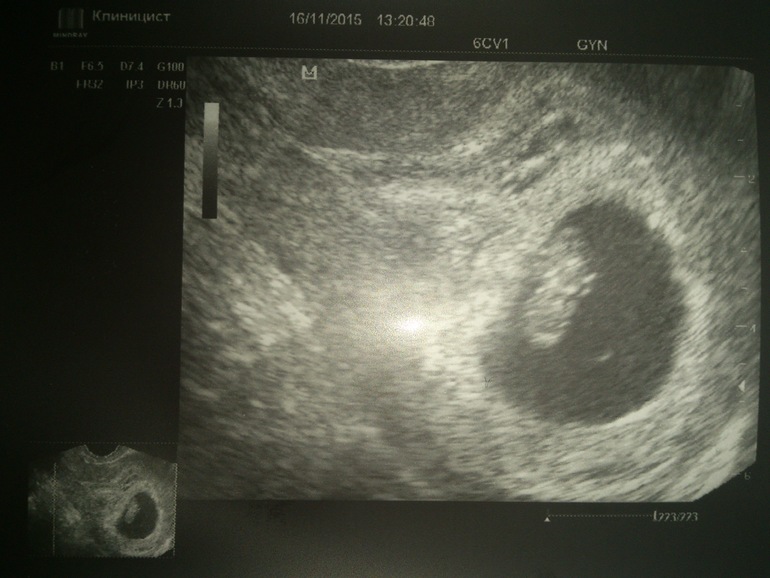

УЗИ, КТГ, доплерВчера ходили с мужем на УЗИ.

Наконец-то увидели сладкую причину моей тесной дружбы с унитазом))).

Смотрела как шевелит ручками и ножками.

Дали послушать сердечко. 164 удара в минуту.

КТР 14 мм